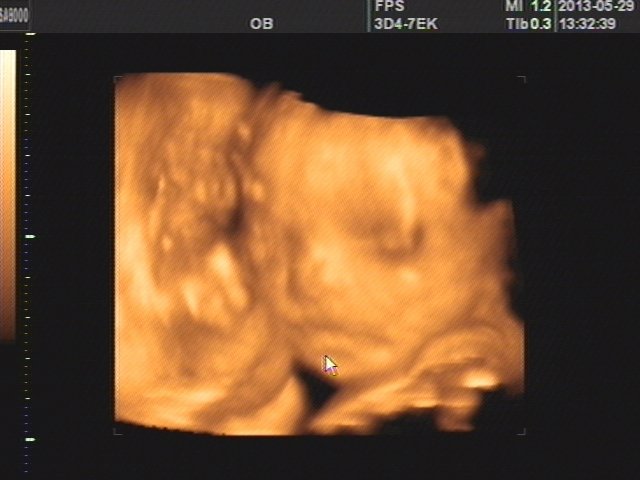

大家帮我看看我宝宝的脸像男孩还是女孩

男孩子吧,比较霸气。,哈哈。 祝您得此龙子。

光看照片看着像男孩

男孩,脸的骨骼,和嘴型能看出来

这个真的很难判断,有长得很漂亮的弟弟,也有长得很壮实的妹妹,要根据父母的长相而定。建议对比下你们夫妻两小时候的照片。像爸爸的是女儿,像妈妈的是儿子。